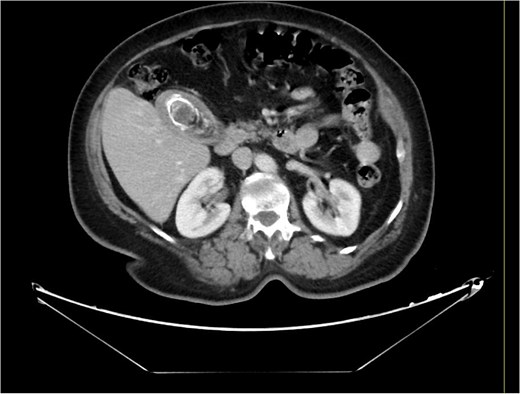

A 63-year-old obese female, known to have hypertension and diabetes, was admitted electively for laparoscopic cholecystectomy and laparoscopic incisional hernia repair with mesh. Prior to surgery, the enhanced computed tomography scan revealed a fat- containing supraumbilical hernia measuring 1.5 cm, a 54 mm gallbladder stone, and unremarkable liver pancreas, spleen, kidneys, and pelvis organs, with no evidence of intra-abdominal free air or fluid (Figs 1 and 2). The patient underwent surgery under general anesthetic using standard sterile procedures. We began with a supraumbilical incision ⁓3 cm above the umbilicus over the previous hernial site. After making a 1 cm longitudinal incision, we identified and opened the fascia, introducing a 12 mm port without immediate complications. The camera was inserted, gas was insufflated, and the abdomen was explored, revealing no immediate injury. An additional 11 mm port was inserted in the left upper quadrant for further exploration. Severe adhesions of the small bowel to the abdominal wall were noted. The first port was examined, and no bowel injury was found. LigaSure was utilized for adhesiolysis, followed by the insertion of two 5 mm ports in the right upper and lower quadrants, and a 5 mm port in the epigastric area. Laparoscopic adhesiolysis was performed, releasing the adhesions without bowel injury. The gallbladder, severely adhered to the liver bed, was identified, retracted cephalad, and Calot’s triangle was achieved. The cystic duct was identified, double clipped, and divided, followed by dissection, clipping, and division of the cystic artery. Intraoperatively, we consulted a senior consultant to confirm the anatomy. The critical view of safety was achieved, and the gallbladder was dissected from its bed. Spillage of gallbladder contents occurred, which was suctioned and controlled. The gallbladder was retrieved through the supraumbilical port using an Endobag without complications (Figs 3 and 4). Hemostasis was secured after examining the liver bed, followed by multiple irrigations and suctioning. The hernial defect was examined and found to be a small incisional hernia (⁓1 × 0.2 cm) containing only fat. After releasing the adhesions, a mesh was applied, tailored to the defect size, and secured with endo-tuckers. Hemostasis was ensured, and a JP drain was inserted under vision and secured with Prolene. All parts were removed under vision, and the skin was closed using clips. The patient tolerated the procedure well and was transferred to the Post Anesthesia Care Unit in stable condition.

Computed tomography of the abdomen and pelvis showing a 54 mm gallbladder stone.